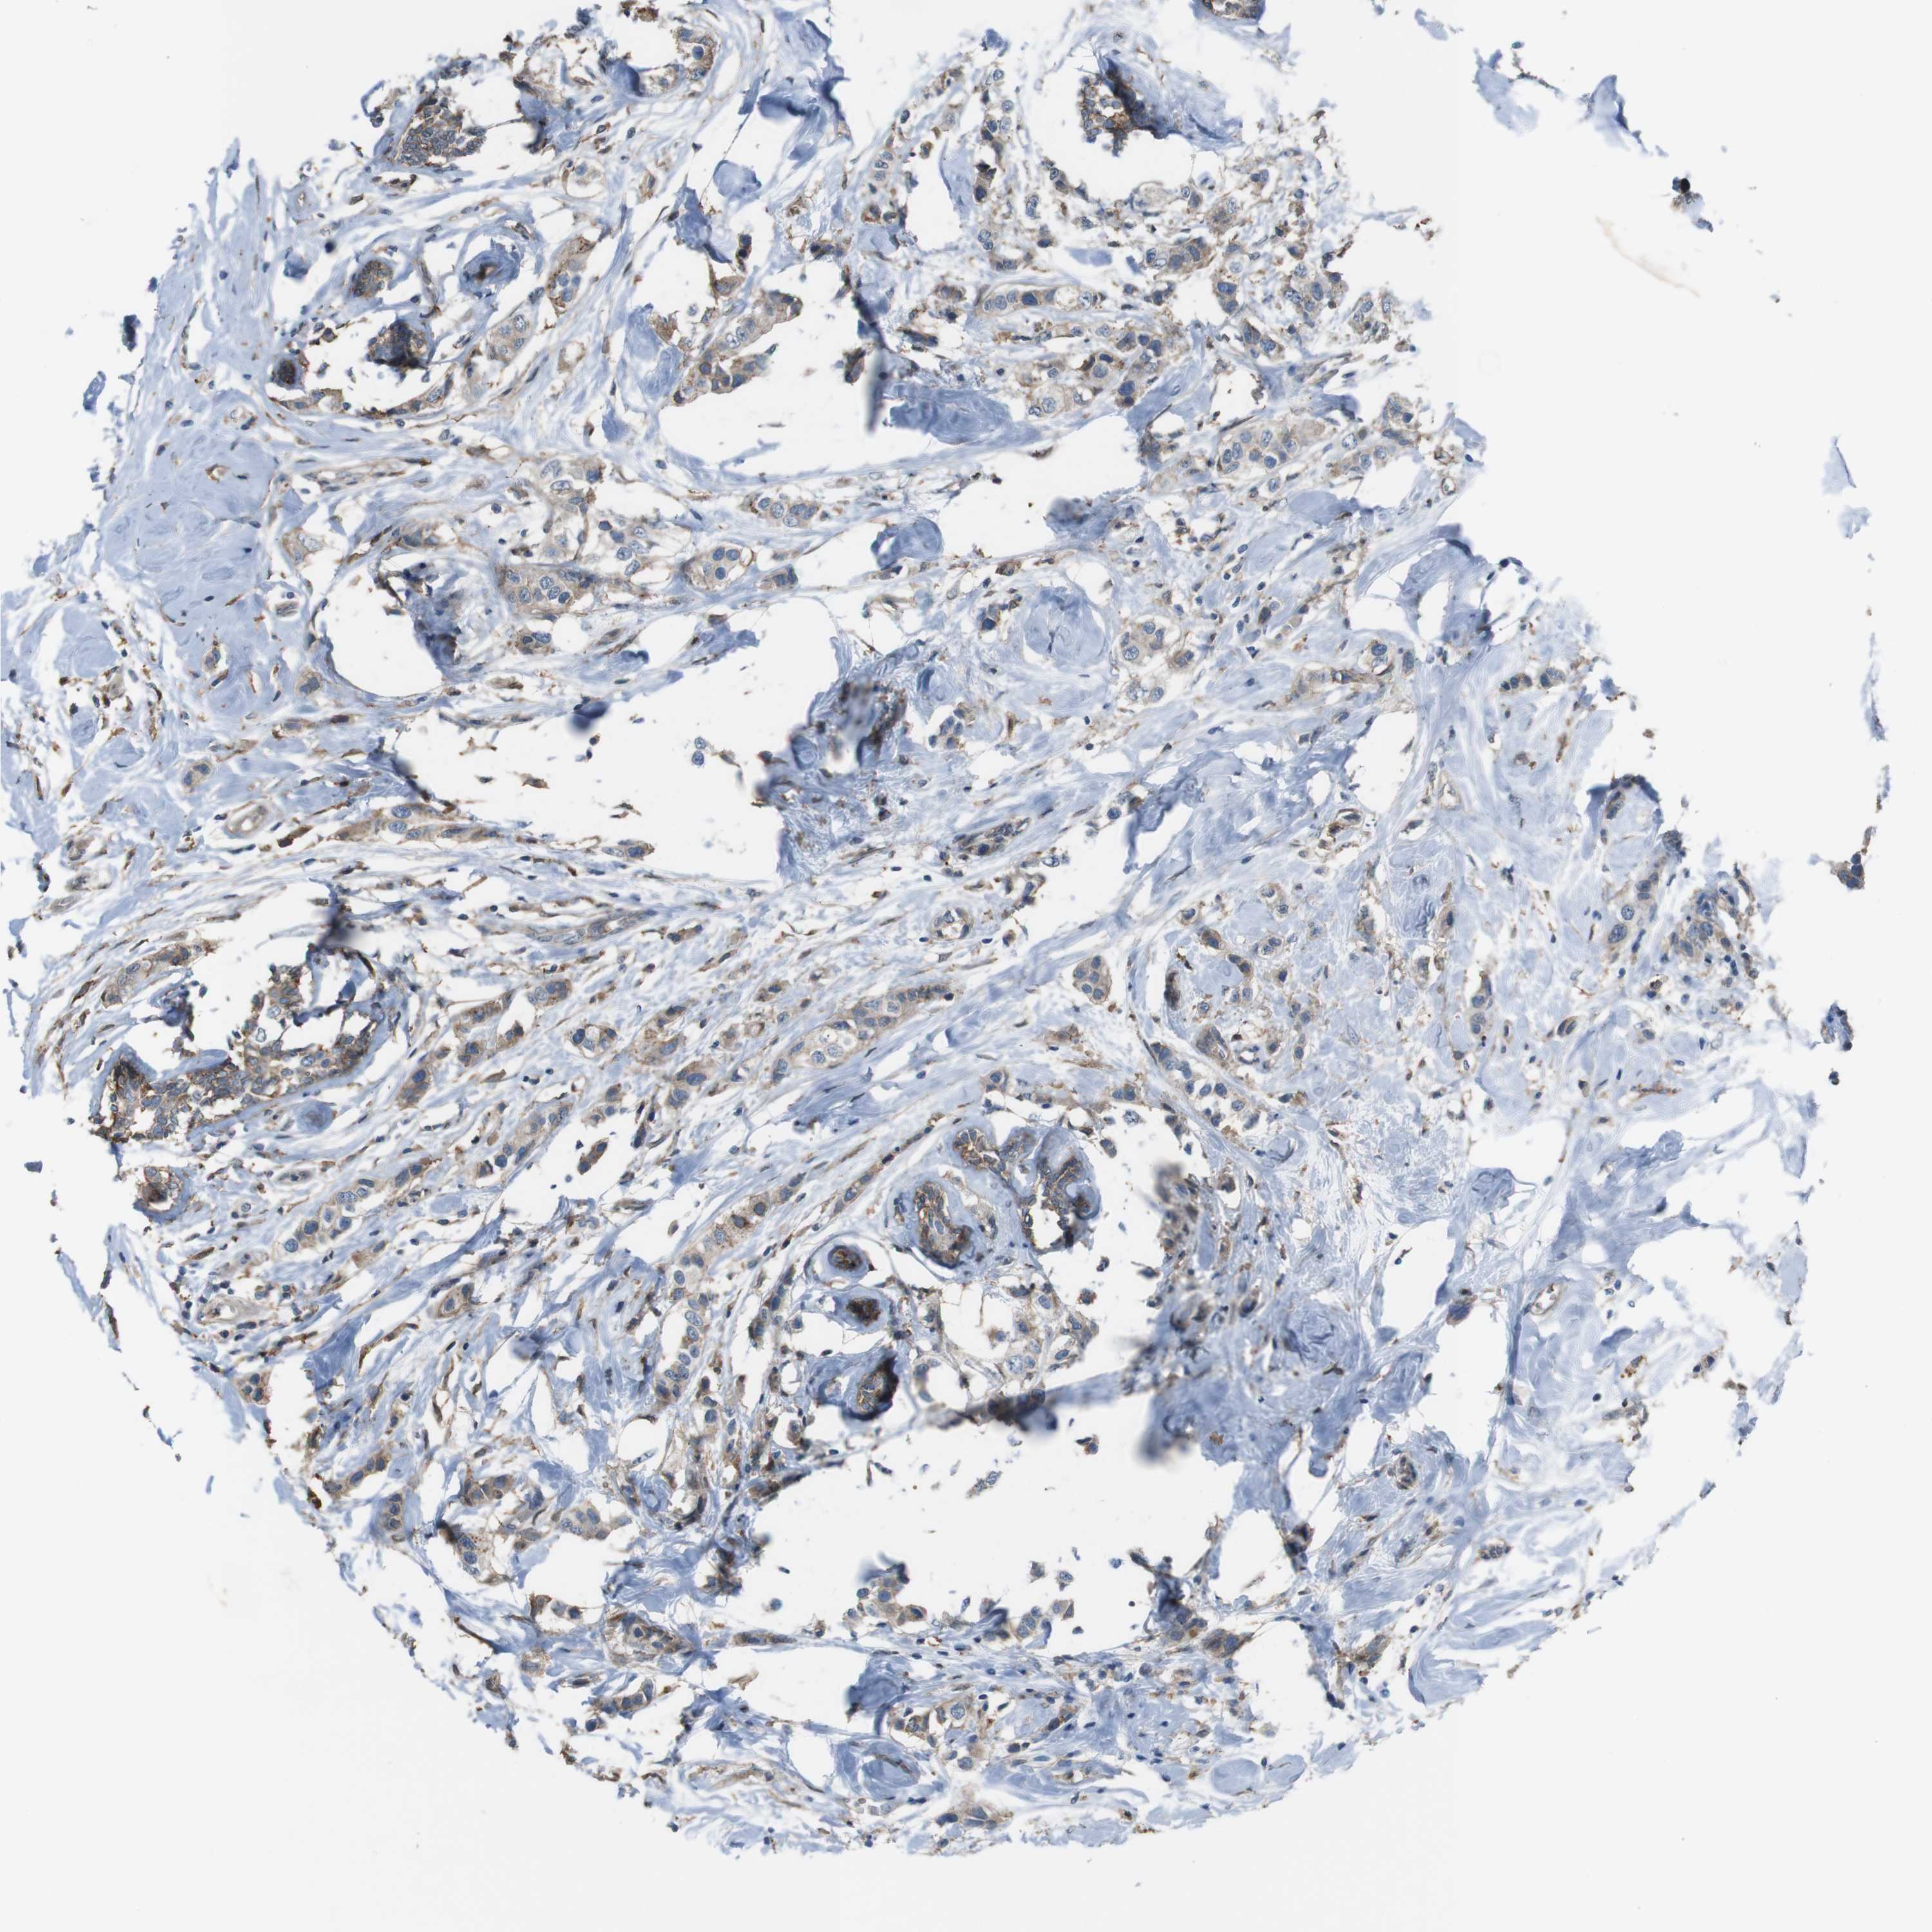

CANCER BREAST CANCER Show tissue menu

BRCA TCGA BRCA VALIDATION PROTEIN EXPRESSION